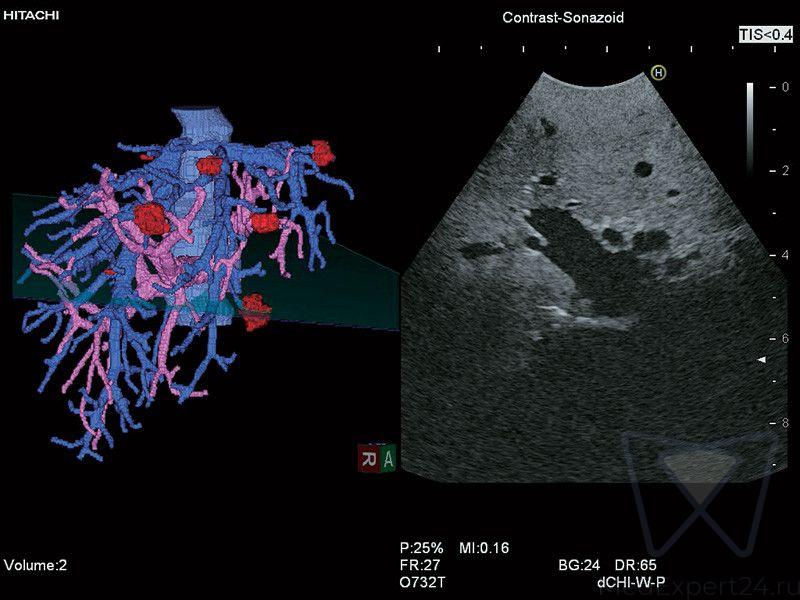

- 3D и 4D изображения,